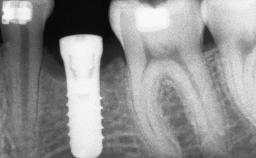

Le Fort I Interpositional Graft and Mandibular Sandwich Osteotomy for Maxillofacial Rehabilitation after Severe Periodontitis

Type of Implants Two-Piece

Bone Augmentation Horizontal|Sinus Floor Elevation|Staged|Vertical

Bone Volume Deficient vertically or deficient vertically AND horizontally